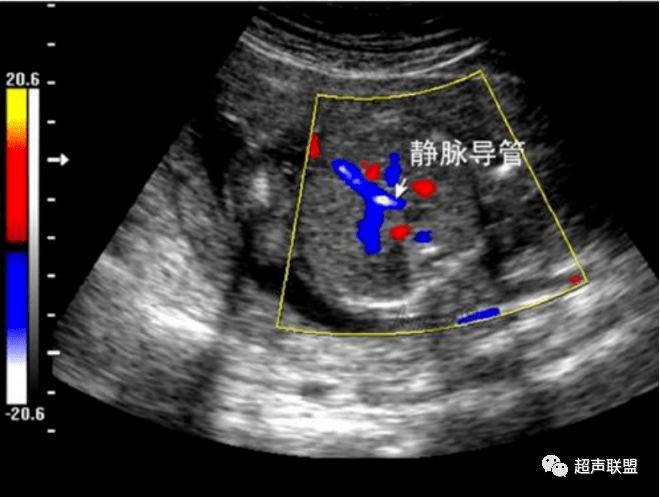

12周静脉导管a波反向

12周静脉导管a波反向,胎儿静脉导管a波反向

dv,a波反向

静脉导管a波反向或消失; 4.脐静脉搏

胎儿静脉导管a波反向

静脉导管a波反向图片

静脉导管超声图

胎儿静脉导管

胎儿静脉导管图

胎儿静脉导管血流频谱

胎儿静脉导管超声切面

正常静脉导管频谱图

胎儿静脉导管超声图片